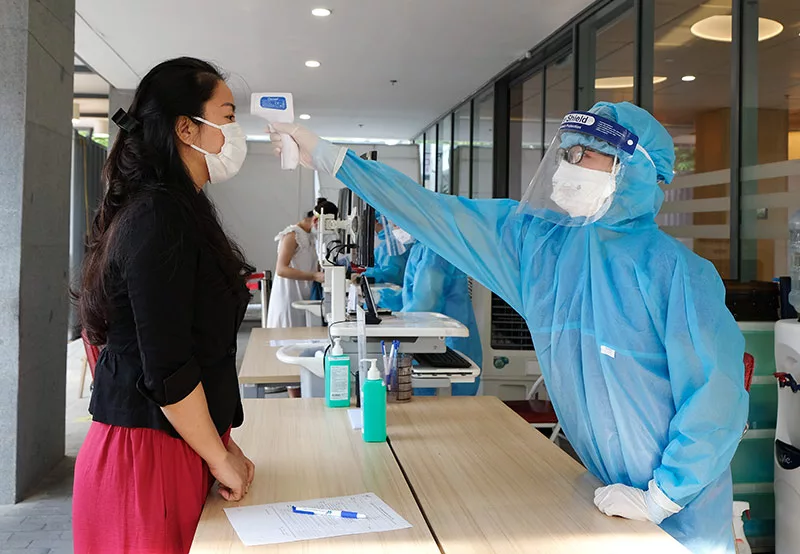

Sốt xuất huyết trong thời kỳ mang thai